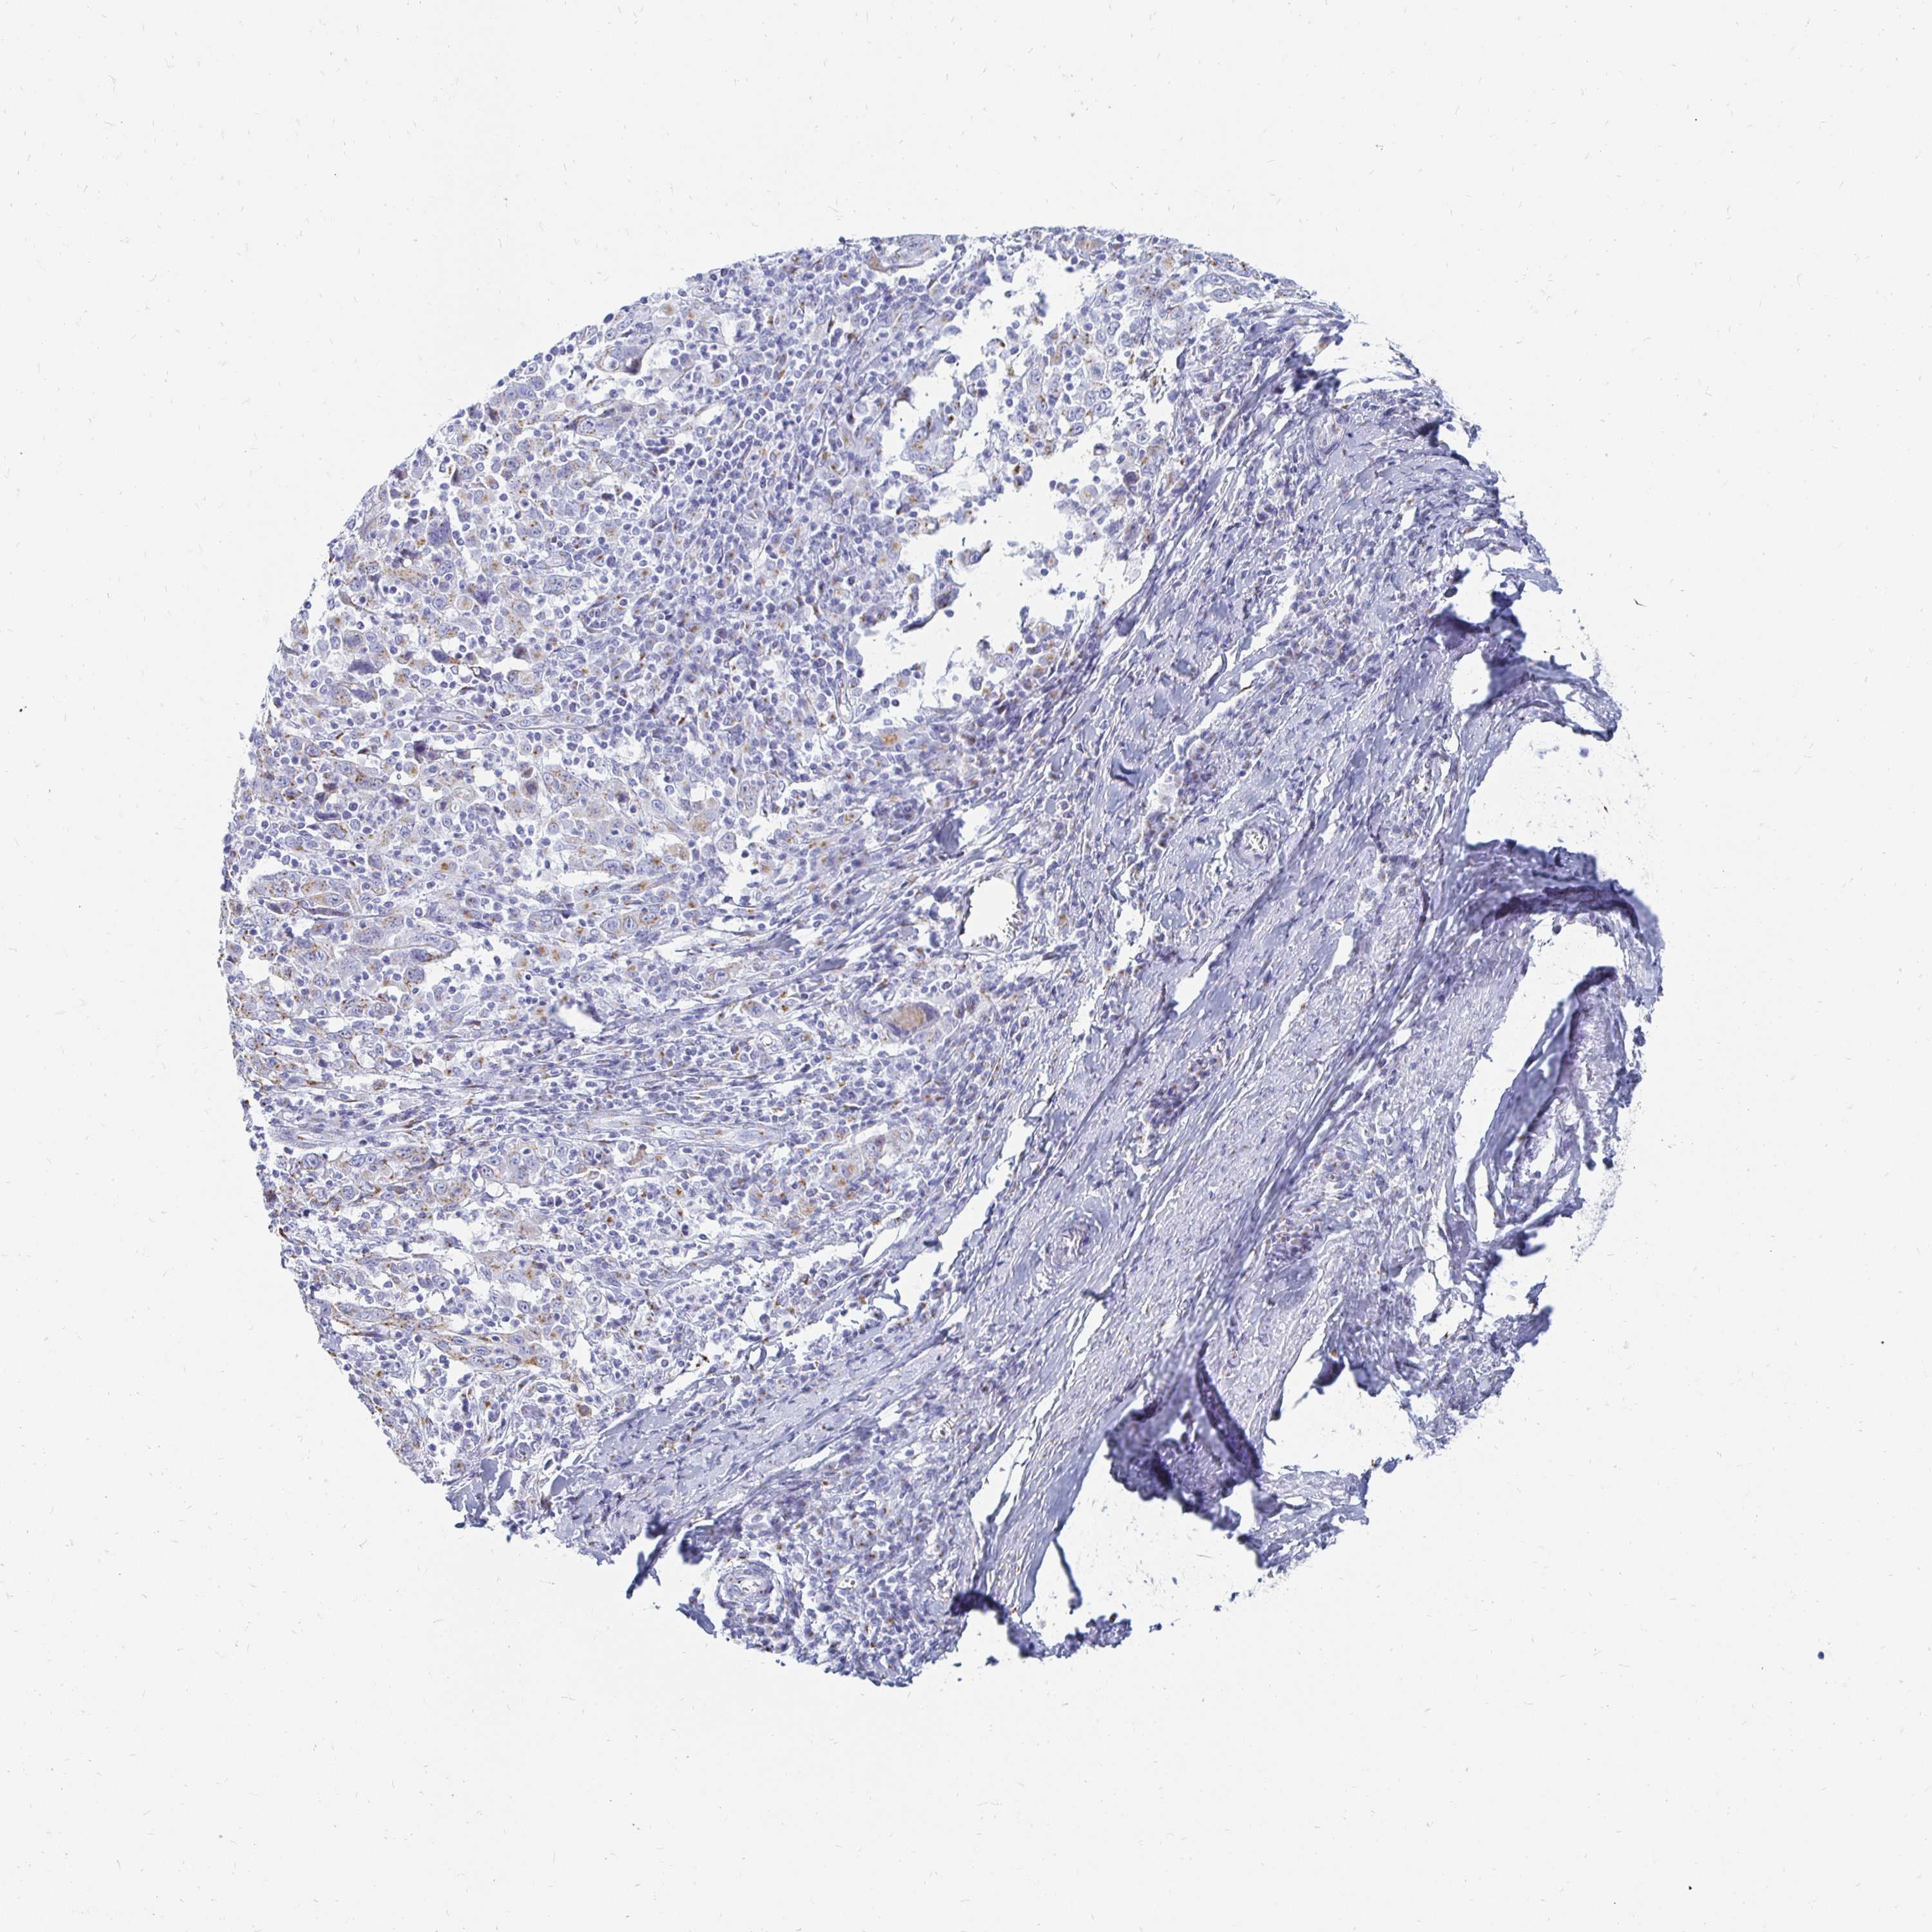

CERVICAL CANCER - Protein expressioni

A mouse-over function shows sample information and annotation data. Click on an image to view it in a full screen mode. Samples can be filtered based on level of antibody staining by selecting one or several of the following categories: high, medium, low and not detected. The assay and annotation is described here.

Note that samples used for immunohistochemistry by the Human Protein Atlas do not correspond to samples in the TCGA dataset.

Antibody stainingi

Antibody staining in the annotated cell types in the current human tissue is reported as not detected, low, medium, or high, based on conventional immunohistochemistry profiling in selected tissues. This score is based on the combination of the staining intensity and fraction of stained cells.

Each image is clickable and will lead to virtual microscopy that enables deeper exploration of all samples and also displays staining intensity scores, fraction scores and subcellular localization as well as patient and tissue information for each sample.

Antibody HPA023880

Staining

High

Medium

Low

Not detected

Intensity

Strong

Moderate

Weak

Negative

Quantity

>75%

75%-25%

<25%

None

Location

Nuclear

Cytoplasmic/membranous

Cytoplasmic/membranous,nuclear

Squamous cell carcinoma, NOS

Adenocarcinoma, NOS